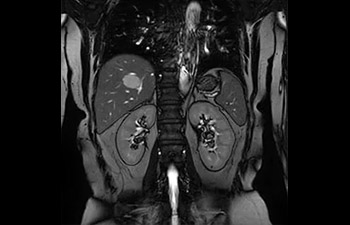

com Compressed SENSE

A equipe de IRM do Hospital Central Kurashiki incorporou o Compressed SENSE à maioria dos protocolos de exames do cérebro, coluna, abdômen e coração do seu Ingenia 1.5T, o que resultou em varreduras de IRM mais rápidas e de alta qualidade, um resultado apreciado por pacientes e pela equipe.